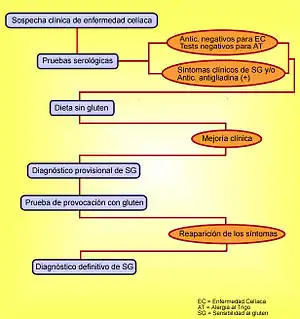

En 2010, la comunidad científica reconoció oficialmente la sensibilidad al gluten no celíaca, en la que todas las pruebas para enfermedad celíaca son normales, pero hay una mejoría con la dieta sin gluten, aproximadamente 30 años después de que fueran descritos los primeros casos.[97][98][40][60]

Palidez de piel y/o mucosas.

Talla baja. Pérdida de peso. Sobrepeso. Hinchazón general fluctuante. Distensión abdominal. Erupciones cutáneas diversas:

- Los anticuerpos anti-gliadina (AGA). Son poco informativos, por lo que ya no se emplean. Los del tipo IgG pueden estar elevados en el 50 % de las personas con sensibilidad al gluten no celíaca.[52][7][153]

- - Pruebas hepáticas: FA, AST, ALT, GGT y Bilirrubina total y fraccionada